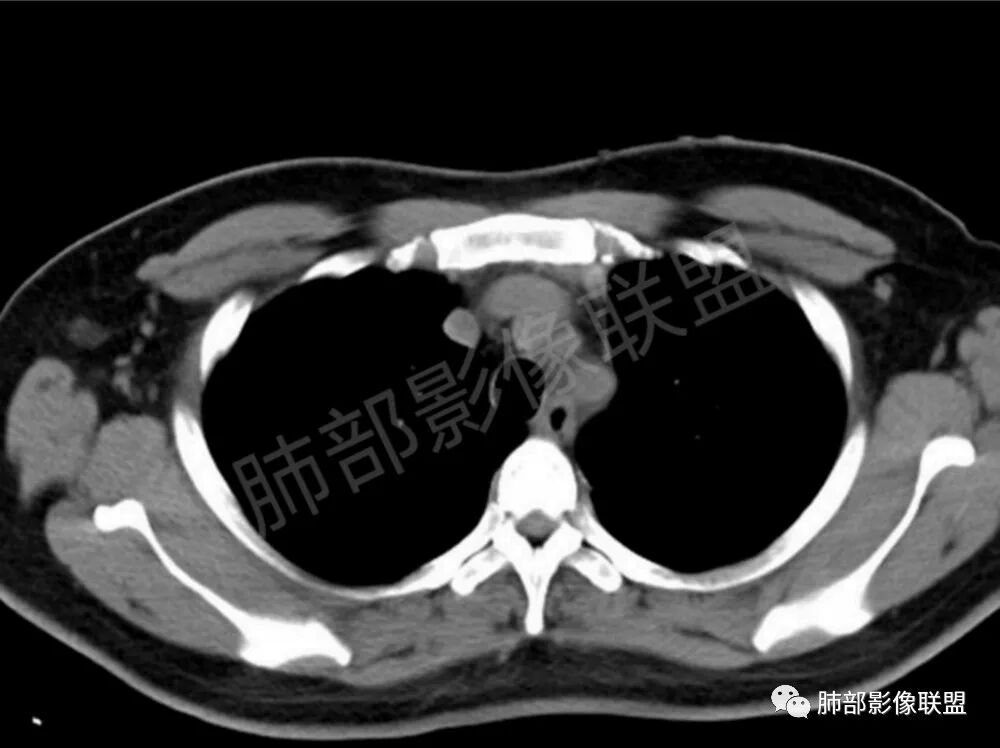

男性,22岁,HIV病史,症状半年,双肺多发大小不等结节影,边缘光滑,密度均匀,以胸膜下分布为主,部分与胸膜相连,胸膜下脂肪间隙可见,病灶近段支气管走行病灶内,远端似有堵塞,无增强图像,考虑隐球菌,鉴别:淋巴瘤,GPA

双肺多发结节影,膨隆,边缘光滑,圆顿,沿支气管血管束分布为主,部分贴胸膜,部分见空洞,空气支气管征

两肺多发结节性,大部分位于胸膜下,部分结节周围可见晕征。局部结节内可见扩张的支气管,纵隔淋巴结大,脾大,22岁男,HIV阳性,常规先考虑隐球菌。鉴别淋巴瘤,结核,马儿。

男,22,半年前咳嗽伴少痰,查HIV阳性,痰查TB阳性,既往有肺部斑片影伴空洞、纵隔淋巴结肿大、脾大。SCC、CA50、CA199、FER增高,此次胸部CT:两肺多发结节影,部分沿血管束分布,部分贴胸膜下,大小不一,密度不一,部分较散、边缘模糊,部分较实、圆钝、周围模糊晕,部分结节有支气管进入穿行自然,部分结节有血管分支自如通过。考虑HI∨相关淋巴增殖类病变,淋巴瘤?LYG?鉴别PC、TB。

青年男性,半年前咳嗽,HIV阳性,结核DNA阳性,肿标糖类抗原和铁蛋白增高。外院影像有纵隔淋巴结增大伴脾大,肺部病灶空洞。现在影像:肺内多发沿支气管分布(有支气管充气征,长轴沿支气管分布)及胸膜下分布(平行于胸膜)的大小不等结节,个别伴有空洞,双侧腋窝淋巴结肿大。纵隔图片不够,是否还有淋巴结肿大未知,脾脏未显示。

1.双肺多发大小不一结节,外围为主,边界尚清,部分周围似有GGO

2.类圆形,部分与胸膜相连,糊墙

3.支气管通畅或近端堵塞

影像学缺乏特征性,以支气管血管周围、胸膜下及双肺下叶周边多发结节影最多见,结节易坏死形成空洞,伴有游走性和多变性的特征,结节周围可有磨玻璃样晕征,有时也可见单发结节影、薄壁的囊状阴影或弥漫性浸润影。肺门、纵隔淋巴结肿大少见, 可见胸腔积液和气胸。